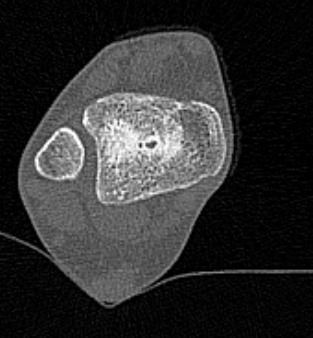

Во время исследования рентгеновская трубка томографа вращается вокруг исследуемой области и производит множество послойных снимков с шагом от 0,5 мм. Полученные снимки поперечного сечения с помощью компьютерной программы могут быть преобразованы в 3D-изображения исследуемого органа. Это позволяет выявлять различные патологические процессы на начальных стадиях и назначать своевременное лечение.

За счет быстроты, доступности и неинвазивности (то есть исследование не требует вмешательства в организм) метод КТ особенно востребован в ортопедии и травматологии. Мультиспиральная КТ лучше всего визуализирует плотные ткани, такие как кости и хрящи. Поэтому, в первую очередь, применяется для диагностики травм суставов (вывихов, подвывихов, переломов).

В отличие от обычного рентгена, при котором изображения костных структур накладываются друг на друга, что затрудняет диагностику, компьютерная томография дает возможность увидеть объемную модель сустава, наглядно оценить пространственное соотношение внутрисуставных структур, суставных поверхностей, расположение костных отломков при переломах и травмах. Это особенно важно в ходе подготовки к оперативному вмешательству и в послеоперационном периоде для оценки успешности проведенной операции.